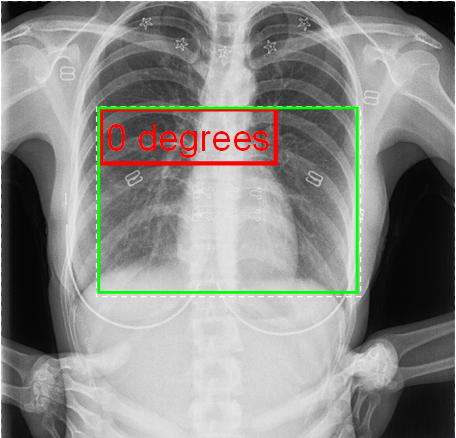

Auto-sizing is most useful when combined with showing a box around the text, or adding a line from the text to an "anchor point", as well as when adding "child labels" to the corners (.NET only). Previous versions have supported autosize as a simple Boolean, but with an obscure (user requested) means to specify that only the height should be shrunk, with the width remaining unchanged. These are being combined, with the addition (for consistency if nothing else) of a new option to preserve height but not width. As in all cases below, the dotted line indicates the defined "Area" of the label, and red indicates what is actually displayed:

This is where the major complications arise, compounded by the different wishes of different developers. Before looking at the new model, I review the issues with the existing one. In the existing model, all works well if the text is allowed to rotate with the image (RotateTextWithImage = true), as all aspects of the label rotate in unison - e.g.